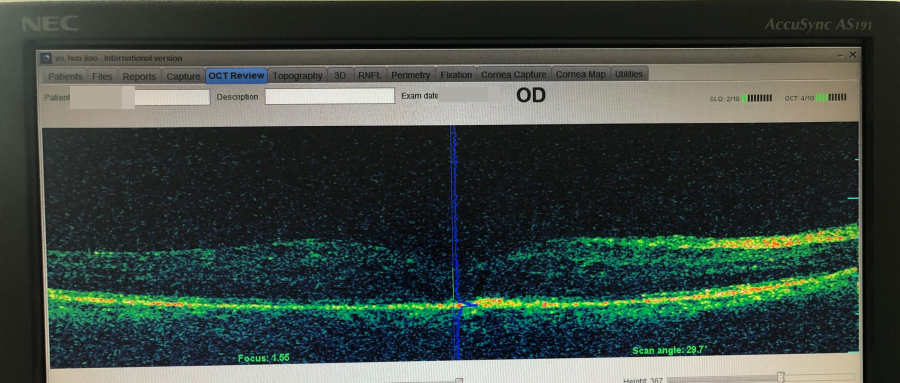

經過OCT光學相干斷層掃描及相關檢查發(fā)現(xiàn),老人右眼視力僅有0.02,右眼眼底出現(xiàn)黃斑水腫,水腫高度為770μm。

▲微脈沖激光治療前,黃斑部位明顯突出

“醫(yī)生說,本來這里應該是略微凹進去的,可從片子上看,反而腫得就像個小山包一樣!”正是異常的水腫影響了視力。

張偉君說,在黃斑疾病門診,父親先后接受了兩次微脈沖激光治療。此后,黃斑水腫高度消退到200μm,效果非常明顯!

▲微脈沖激光治療后,黃斑部位對比明顯